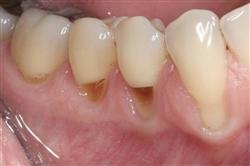

Normally gum tissue surrounds and protects the delicate roots of your teeth. Exposed tooth roots are prone to tooth decay, root canals, discoloration and actual jawbone loss. All of this can lead to tooth loss in advanced cases.

Functional Soft Tissue Grafting replaces the missing gum tissue and protects your teeth. For this reason, soft tissue grafting may be recommended even for back teeth.